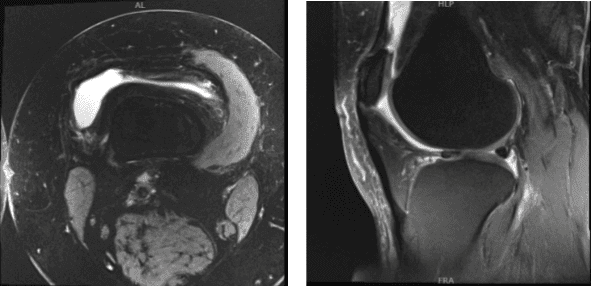

MRI results discussed and found out that there is moderate chondromalacia over the median ridge and medial facet of patella, with varying degrees of chondral surface fissuring and fraying.

Small joint effusion and lateral meniscus tear was also observed. By this time the patient decided to do rest and physical therapy and take naproxen and advised to return when no improvement happened.

MRI – Right Knee Non-Contrast